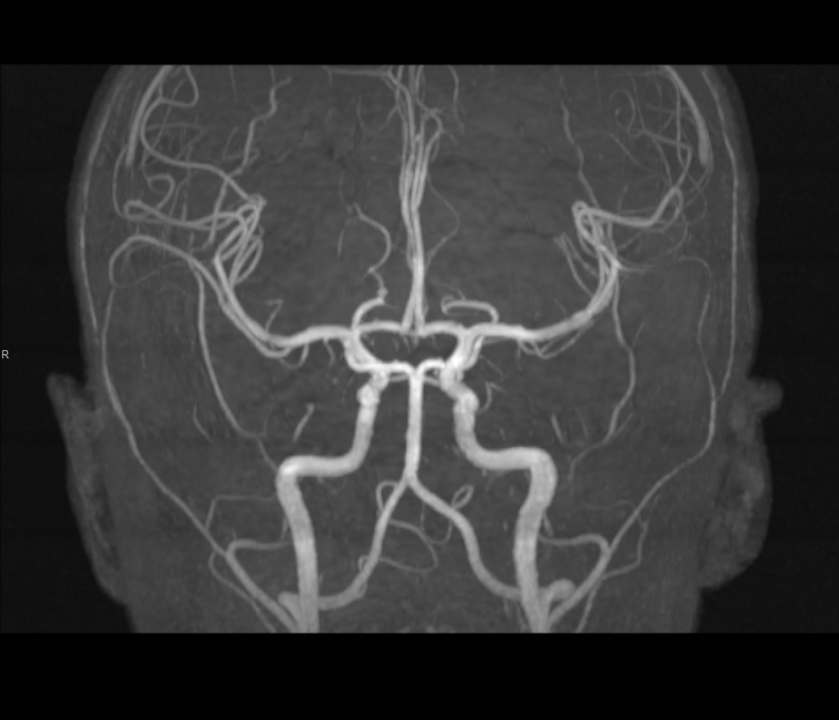

Tijekom Tjedna mozga Poliklinika Affidea Vita daje 20 posto popusta na magnetsku rezonancu!

Povodom obilježavanja Tjedna mozga od 11.

MR angiografija